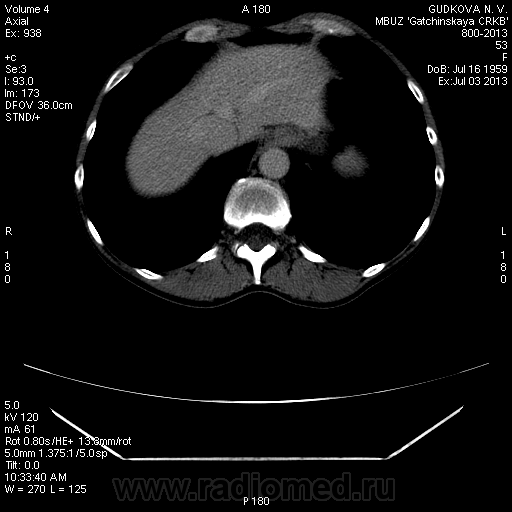

Пациентка Г. 1959 г/р, обратилась амбулаторно в Гатчинскую ЦРКБ на МСКТ брюшной полости, по направлению поликлиники, диагноз: "Образование правой доли печени". По данным УЗИ: гипоэхогенное образование в правой доле печени (сегмент не указывают) 1,1 * 1,1 см; диффузные изменения ПЖЖ, двусторонний нефроптоз. КТ рекомендовано специалистом УЗД.

Сегодня, 3.07.13., выполнена МСКТ органов брюшной полости с болюсным контрастированием (омнипак-300 - 100 мл) на программе "3 фазы печени"

На преконтрастной серии - впечатление о расширении нижней полой вены.

В артериальную фазу - интенсивное накопление контраста, как раз в области этого расширения, в 4-5 сегментах печени.Выше и ниже - идет неизмененная НПВ, без контраста (фаза артериальная!) В венозную фазу - небольшая гиперденсная зона перикавально в печени - и все.

Этот участок патологического накопления контраста имеет размер 2,5 * 2,5 см, никак не 1,1 * 1,1(как дают УЗИ-сты)